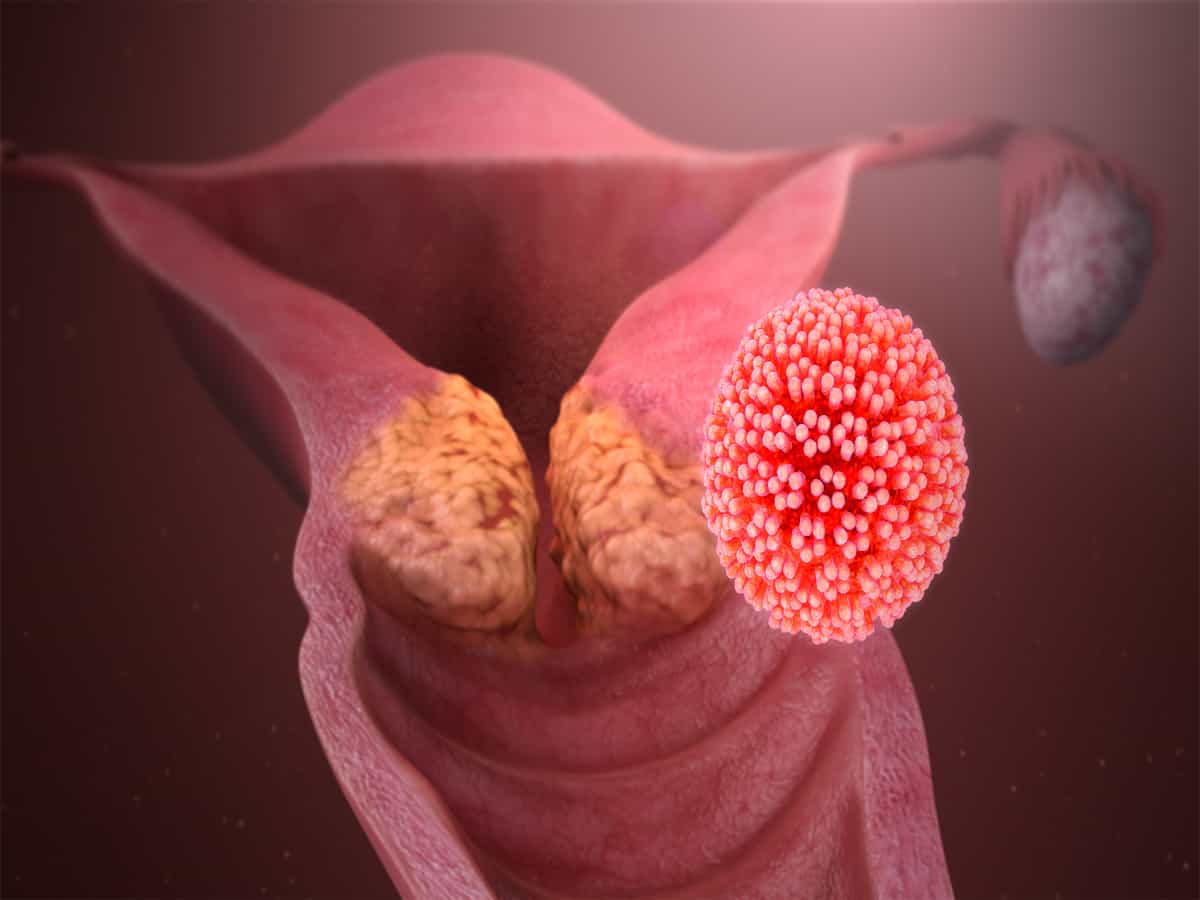

Кондиломы - это одно из самых распространенных заболеваний, передающихся половым путем. Они вызваны вирусом папилломы человека (ВПЧ) и могут появляться на внешних половых органах, анусе, ротовой полости и других областях тела.

Симптомы кондилом могут варьироваться, и визуальное представление этого заболевания может быть различным. Некоторые кондиломы выглядят как небольшие бугорки или бородавки, в то время как другие могут иметь форму плоских пятен или цветных наростов.